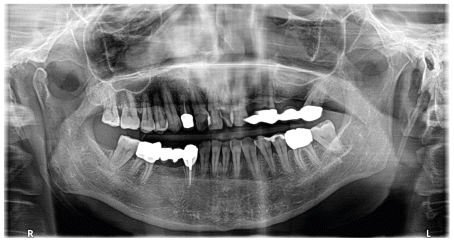

Consequently, a preliminary radiographic assessment, consisting of an Orthopedic CT (OPG), was performed to confirm the clinical hypothesis. The OPG revealed a significant loss of both bone support and dental substance, thus rendering the avulsion of the prosthetic bridge’s abutment teeth advisable.

In agreement with the patient, to restore normal function, the decision was made to proceed with a three-implant, screw-retained implant-prosthetic rehabilitation. To avoid more invasive surgery, such as a maxillary sinus lift, which would otherwise be necessary given the limited bone support, and to avoid placing implants in post-extraction sites, three implants with sinus bypass are planned: one straight implant at the position.

2.4 and two tilted implants at positions 2.6 and 2.7, with immediate loading.